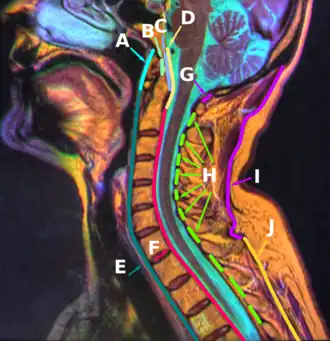

En anatomie humaine, le ligament longitudinal antérieur (ou ligament vertébral commun antérieur) est une longue bande fibreuse descendant verticalement de la face externe de l'os occipital jusqu'à la face antérieure de la deuxième vertèbre sacrée (S2). Il adhère au périoste de la face antérieure des corps vertébraux et aux disques intervertébraux[1][source insuffisante]. Il forme une jointure fibreuse de la colonne vertébrale.

Le ligament longitudinal antérieur s’insère sur la face exocrânienne de la partie basilaire de l'os occipital.

Le ligament est épais et légèrement plus étroit sur les corps vertébraux et plus mince mais légèrement plus large sur les disques intervertébraux.

Entre l'os occipital et l'atlas, le ligament est une étroite bandelette qui s'élargit peu à peu de haut en bas.

Il se poursuit verticalement sur la face antérieure des corps vertébraux et des disques intervertébraux.

Après la troisième vertèbre thoracique le ligament s'étend sur les faces latérales des corps vertébraux jusqu'aux articulations costo-vertébrales.

En région lombaire, la partie latérale du ligament disparaît et le ligament s'étend seulement sur la face antérieure des corps vertébraux.

En région sacrale, le ligament recouvre la première vertèbre sacrée puis se termine sur la deuxième vertèbre sacrée[2][source insuffisante].

Les fibres se répartissent sur trois couches : une superficielle qui relie trois à quatre vertèbres, une intermédiaire qui relie deux à trois vertèbres et une profonde qui relie les vertèbres voisines.